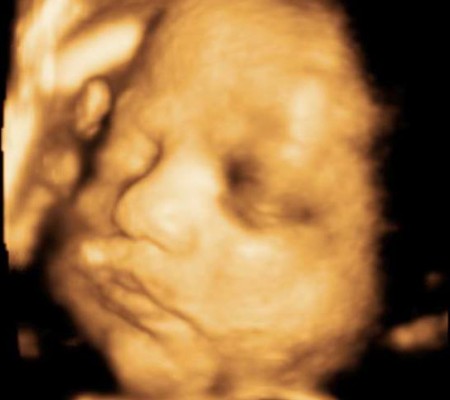

3D i 4D tehnologija omogućava da vidimo površinu bebe na lepši način i pokrete ploda u realnom vremenu.

Takođe nam omogućava da bolje vidimo fetalne mane na licu, šakama i stopalima.

Kao i 2D, 3D i 4D koriste ultrazvučni talas da se kreira slika bebe u materici. 3D je kreirana slika u prostoru dok 4D prikazuje pokret unutar materice pa možemo videti kako se beba smeje, mršti ili zeva.

Da bi se dobile dobre slike poželjno je da se pregled radi između 24 i 32 nedelje trudnoće.